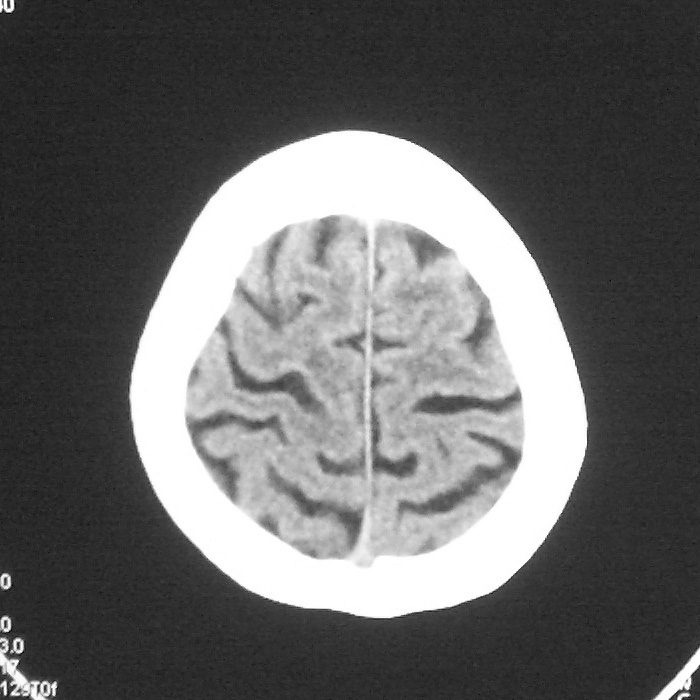

f,70y,口角歪斜、流涎、吐词不清三天

左侧大脑基底节区点状低密度影,边缘清楚,左侧腔梗或软化灶,没什么问题啊?

左侧半卵圆中心腔梗应当比较明确,右侧基底节好象不明显,不好说,做个mri明确吧

右侧基底,左侧半卵圆中心腔梗

1、右侧基底,左侧半卵圆中心腔梗。2脑萎缩。

左侧腔隙性梗塞灶,脑萎缩。

左侧基底节区示点状低密度灶,边界清楚,密度均匀,余所示无著变。

意见:腔隙性脑梗塞(左基底节区)

各位老师,报告这么写可以吗?右侧我没有看出来。

具体位置我认为应该写左侧放射冠腔梗

左侧半卵圆中心,右侧基底节腔梗。再加个脑萎缩吧